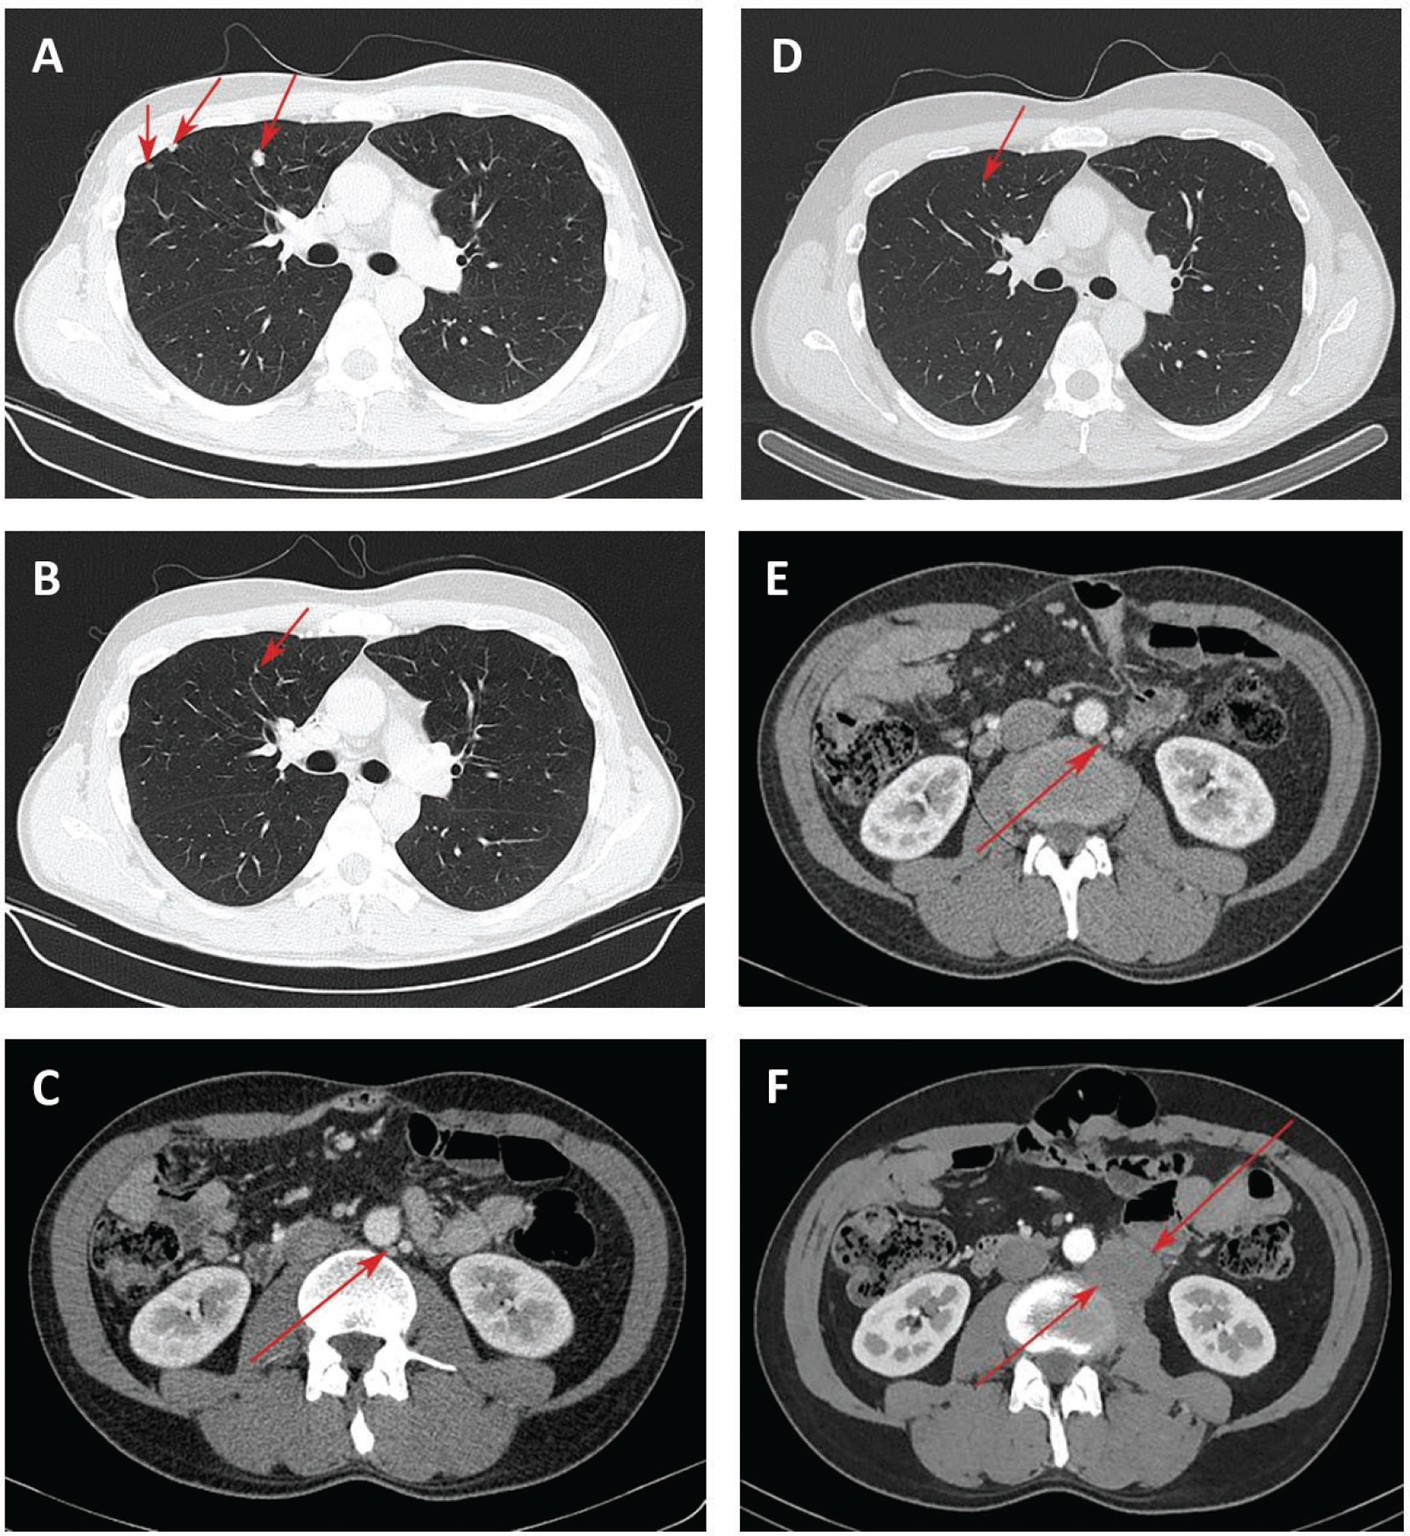

Second-line treatment with FOLFIRI and aflibercept (aflibercept 4 mg/kg on day 1, irinotecan 180 mg/m2 on day 1, leucovorin 400 mg/m2 on day 1, 5-fluorouracil 400 mg/m2 bolus injection followed by 46-hour continuous infusion of 5-fluorouracil 2,400 mg/m2) was initiated. Repeat CT images after three cycles showed no growth of focal nodules in the lung. This treatment was associated with adverse events such as of grade 2 hypertension, nausea, and thrombocytopenia. CT assessment after seven cycles of treatment confirmed a stable response. Due to an acute exacerbation of mixed etiology hepatitis (chronic hepatitis B with serum hepatitis B virus DNA titer >105 copies/mL and toxic hepatitis) and an abnormal alanine aminotransferase exceeding nine times the upper limit of normal at baseline, subsequent treatment was interrupted. The patient received hepatoprotective and detoxification treatment. Approximately 2 months later, CT scans showed an increase of nodule size in the lung (Fig. 2A).

Fig. 2 - Chest computed tomography (CT) of the lung lesions and para-aortic lymph node lesion. Focal nodules in the lung at start of nivolumab treatment (A); 5 months after nivolumab treatment, reduction of lung nodules (B) and para-aortic lymph node lesion up to 12 mm (C); 8 months after nivolumab treatment, disappearance of lung lesions (D) and lack of growth of para-aortic lymph node lesion (E); increase of para-aortic lymph node lesion 40 months after nivolumab treatment (F).

Given the fast progression and PD-L1 status, treatment with nivolumab at a dose 240 mg was started in December 2018. Three months later, most of the previously identified focal nodules in the lung were not clearly visualized by CT, the remaining lesions decreased in size up to 1-2 mm. In May 2019, chest CT scans confirmed the reduction of lung nodules (Fig. 2B). However, a para-aortic lymph node (PALN) on the left up to 15×12 mm was found (Fig. 2C). Using the iRECIST as a modified immune RECIST criterion (10), the response was classified as a dissociated response. MSS phenotype in lymph node was further verified by PCR (Fig. 1B).

Further administration of nivolumab allowed achieving positive dynamics in terms of the disappearance of lesions in the lung (Fig. 2D) and the absence of the growth of PALN metastases in August 2019 (Fig. 2E). An immune stable disease (iSD) per iRECIST was recorded until September 2021, when we had to discontinue treatment due to the patient being infected with COVID-19. The administration of nivolumab was resumed; however, in April 2022, CT scans revealed an increase in the size of PALN by 7 mm compared with the baseline (Fig. 2F). The decision to initiate FOLFOX plus bevacizumab therapy (bevacizumab 5 mg/kg on day 1, oxaliplatin 85 mg/m2 on day 1, leucovorin 400 mg/m2 on day 1, and 5-fluorouracil 400 mg/m2 bolus injection followed by 48 hours continuous infusion of 5-fluorouracil 2,400 mg/m2 on day 1) was taken by a multidisciplinary staff. Due to the experience of hypersensitivity reaction to oxaliplatin after three cycles, the patient was switched to the bevacizumab in combination with capecitabine regimen (bevacizumab 5 mg/kg and capecitabine 2,500 mg/day, days 1 and 14). Currently, the patient has completed 10 cycles of this therapy with good tolerance.